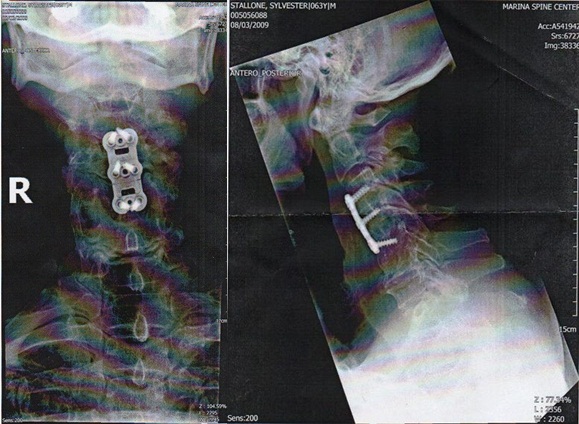

스텔론은 이들의 의혹을 잠재우기 위해 자신의 공식 사이트에 목 안에 철심이 있는 엑스레이 사진을 공개했다. 그는 이 사진과 함께 "의심하는 이들을 위해 천 마디 말보다 이 사진 하나가 더 의미가 있을 것이다. 내가 목 보호대를 한 모습을 보지 못한 이유는 3주 동안 치료를 위해 집에서만 지냈기 때문"이라고 설명했다.